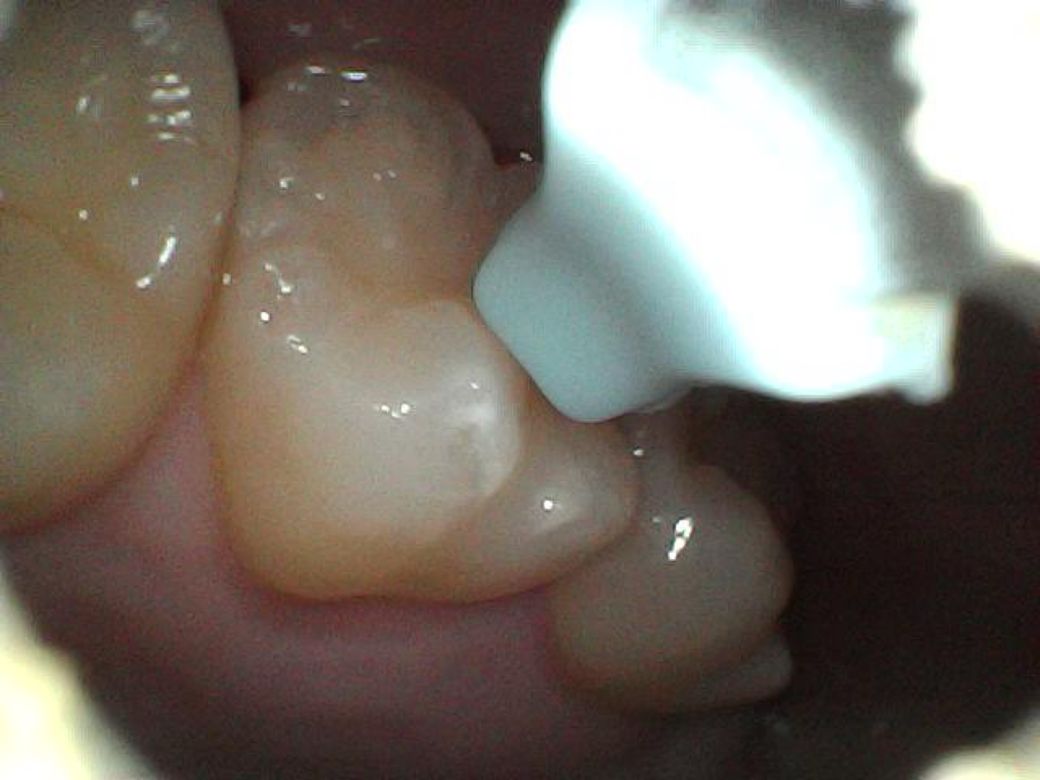

이빨에 뭔가 하얀 것이 생겼어요, 충치인가요?

제가 이

닦고 혀로 스캔하는 버릇이 있는데 그 전까지는 느껴지지 않다가 어제부터 왼쪽 어금니 옆에 만져지는 무언가가 생겼어요.

제가 내시경 귀이개가 있어서 들여다봤는데 치석인지 충치인지 모르겠네요..

혀로 만지는 촉감은 현무암같이 꺼끌꺼끌한 돌덩이 같기도 하고.. 뭔가 부식된 것 같은 촉감도 느껴져요

어제 아침, 오늘 아침 이틀동안 찍은 사진들인데 이거 혹시 사진으로 뭔지 구분이 가능할까요?

처음 두장이 어제, 나머지가 오늘 사진입니다

어제

• 1번 째 사진

• 2번 째 사진